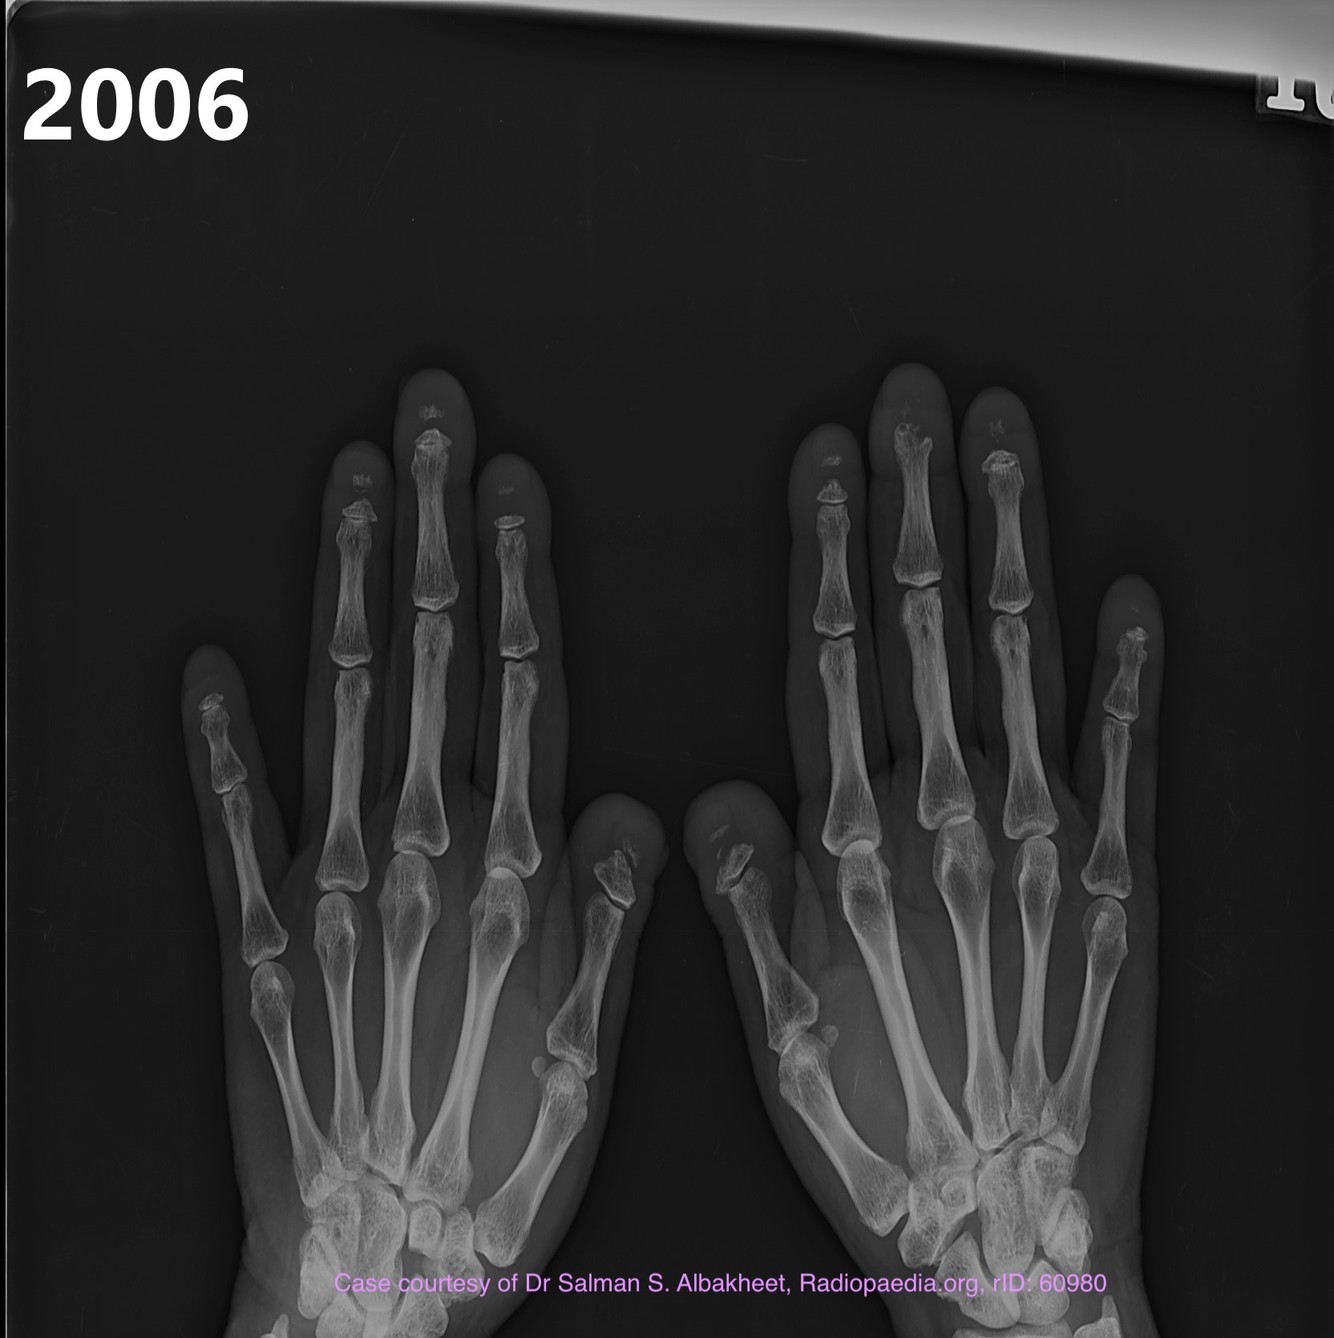

Hands and feet

acro-osteolysis

transverse band of osteolysis in distal phalanges is characteristic

distal to proximal osteolysis is also seen